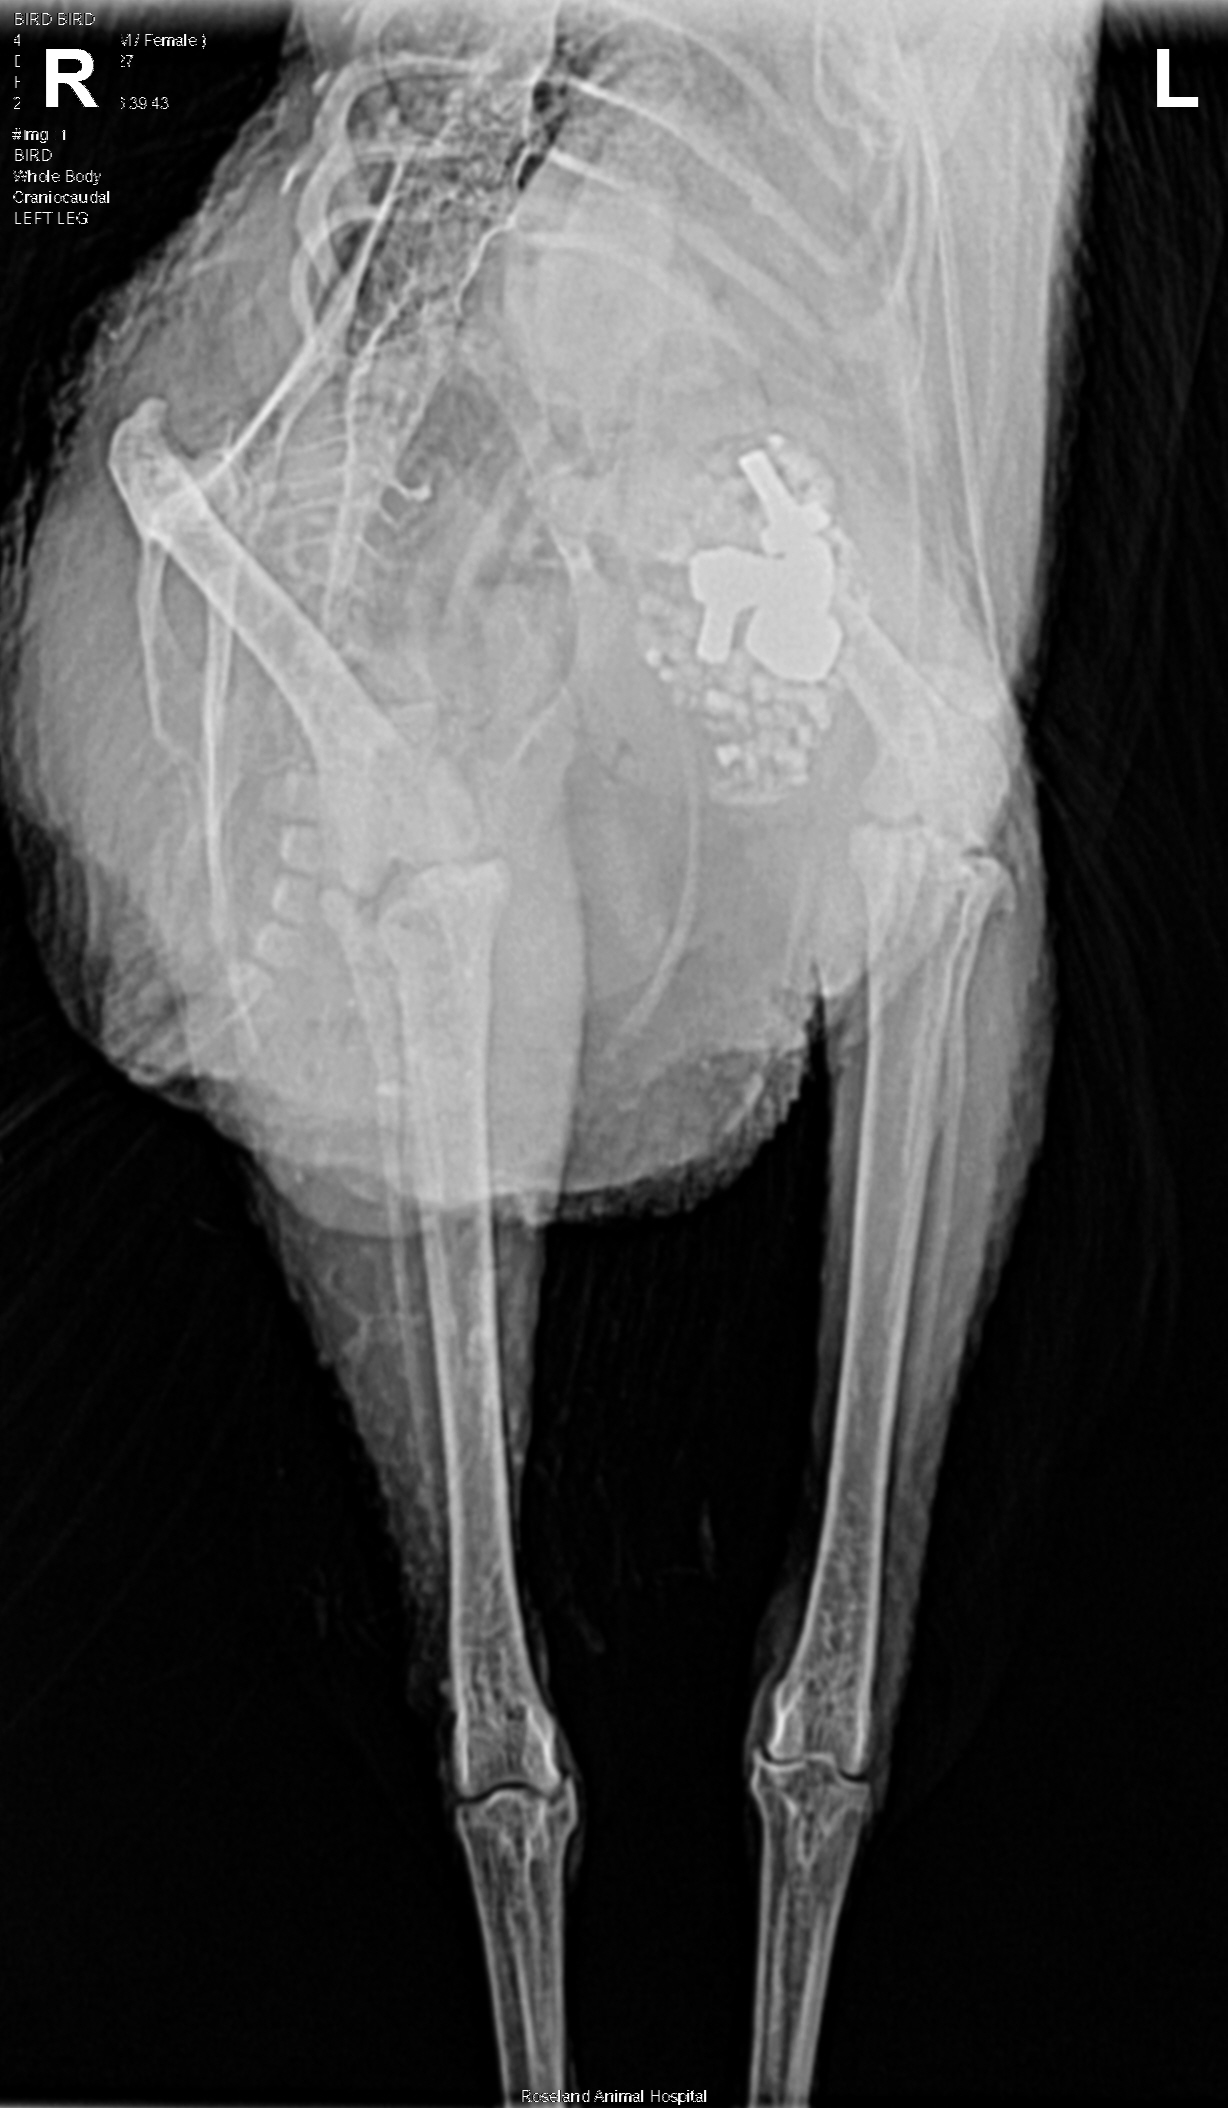

Bird Bird, 13 month-old Australorp x Hen

As a chick Bird Bird incurred a pecking injury and was separated from her brooder mates. For the next couple of months she was raised as a house chicken. Taya has a coop and run, but because Bird Bird was always an outsider she chose to live in the horse barn. They were in the process of building horse stalls and rabbit cages when her husband either dropped some nuts and bolts or the hen found them and ate them.

Taya noticed that Bird Bird was limping (her only symptom) and monitored her for the next 3-4 weeks trying to figure out what was going on. On Valentine’s Day she took her to the veterinarian. Bird Bird’s x-ray revealed a gizzard with some interesting metal bits that weren’t likely to come out on their own.

Her exam was also overall unremarkable beyond the inability to use the left leg. Radiographs (x-rays) were performed in an effort to better visualize the hip joint and the femur as palpation alone is often challenging due to the tight apposition with the body wall. On those radiographs metallic objects were noted in her ventriculus. The soft tissues of her left leg and her bones had no abnormalities.

Given the lameness and the findings on her radiographs, the concern was for a metal toxicity resulting in neurologic deficits/lameness. Bird Bird’s owners made the decision to move forward with a ventriculotomy or incision into the ventriculus to facilitate removal of the foreign material.